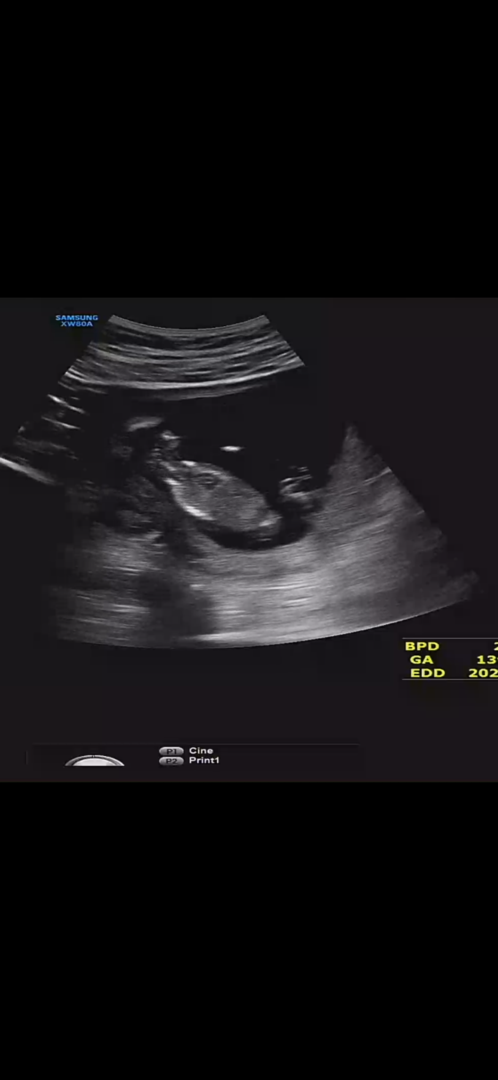

12주차 각도법 봐주세요ㅎㅎ

영상은 안 올라가나봐요ㅜㅠ 혹시 보이는 고수님들 계실까요~?

좀 흐릿하지만 끝이 갈라진 게 보여서 딸 맞을 것 같아요😊